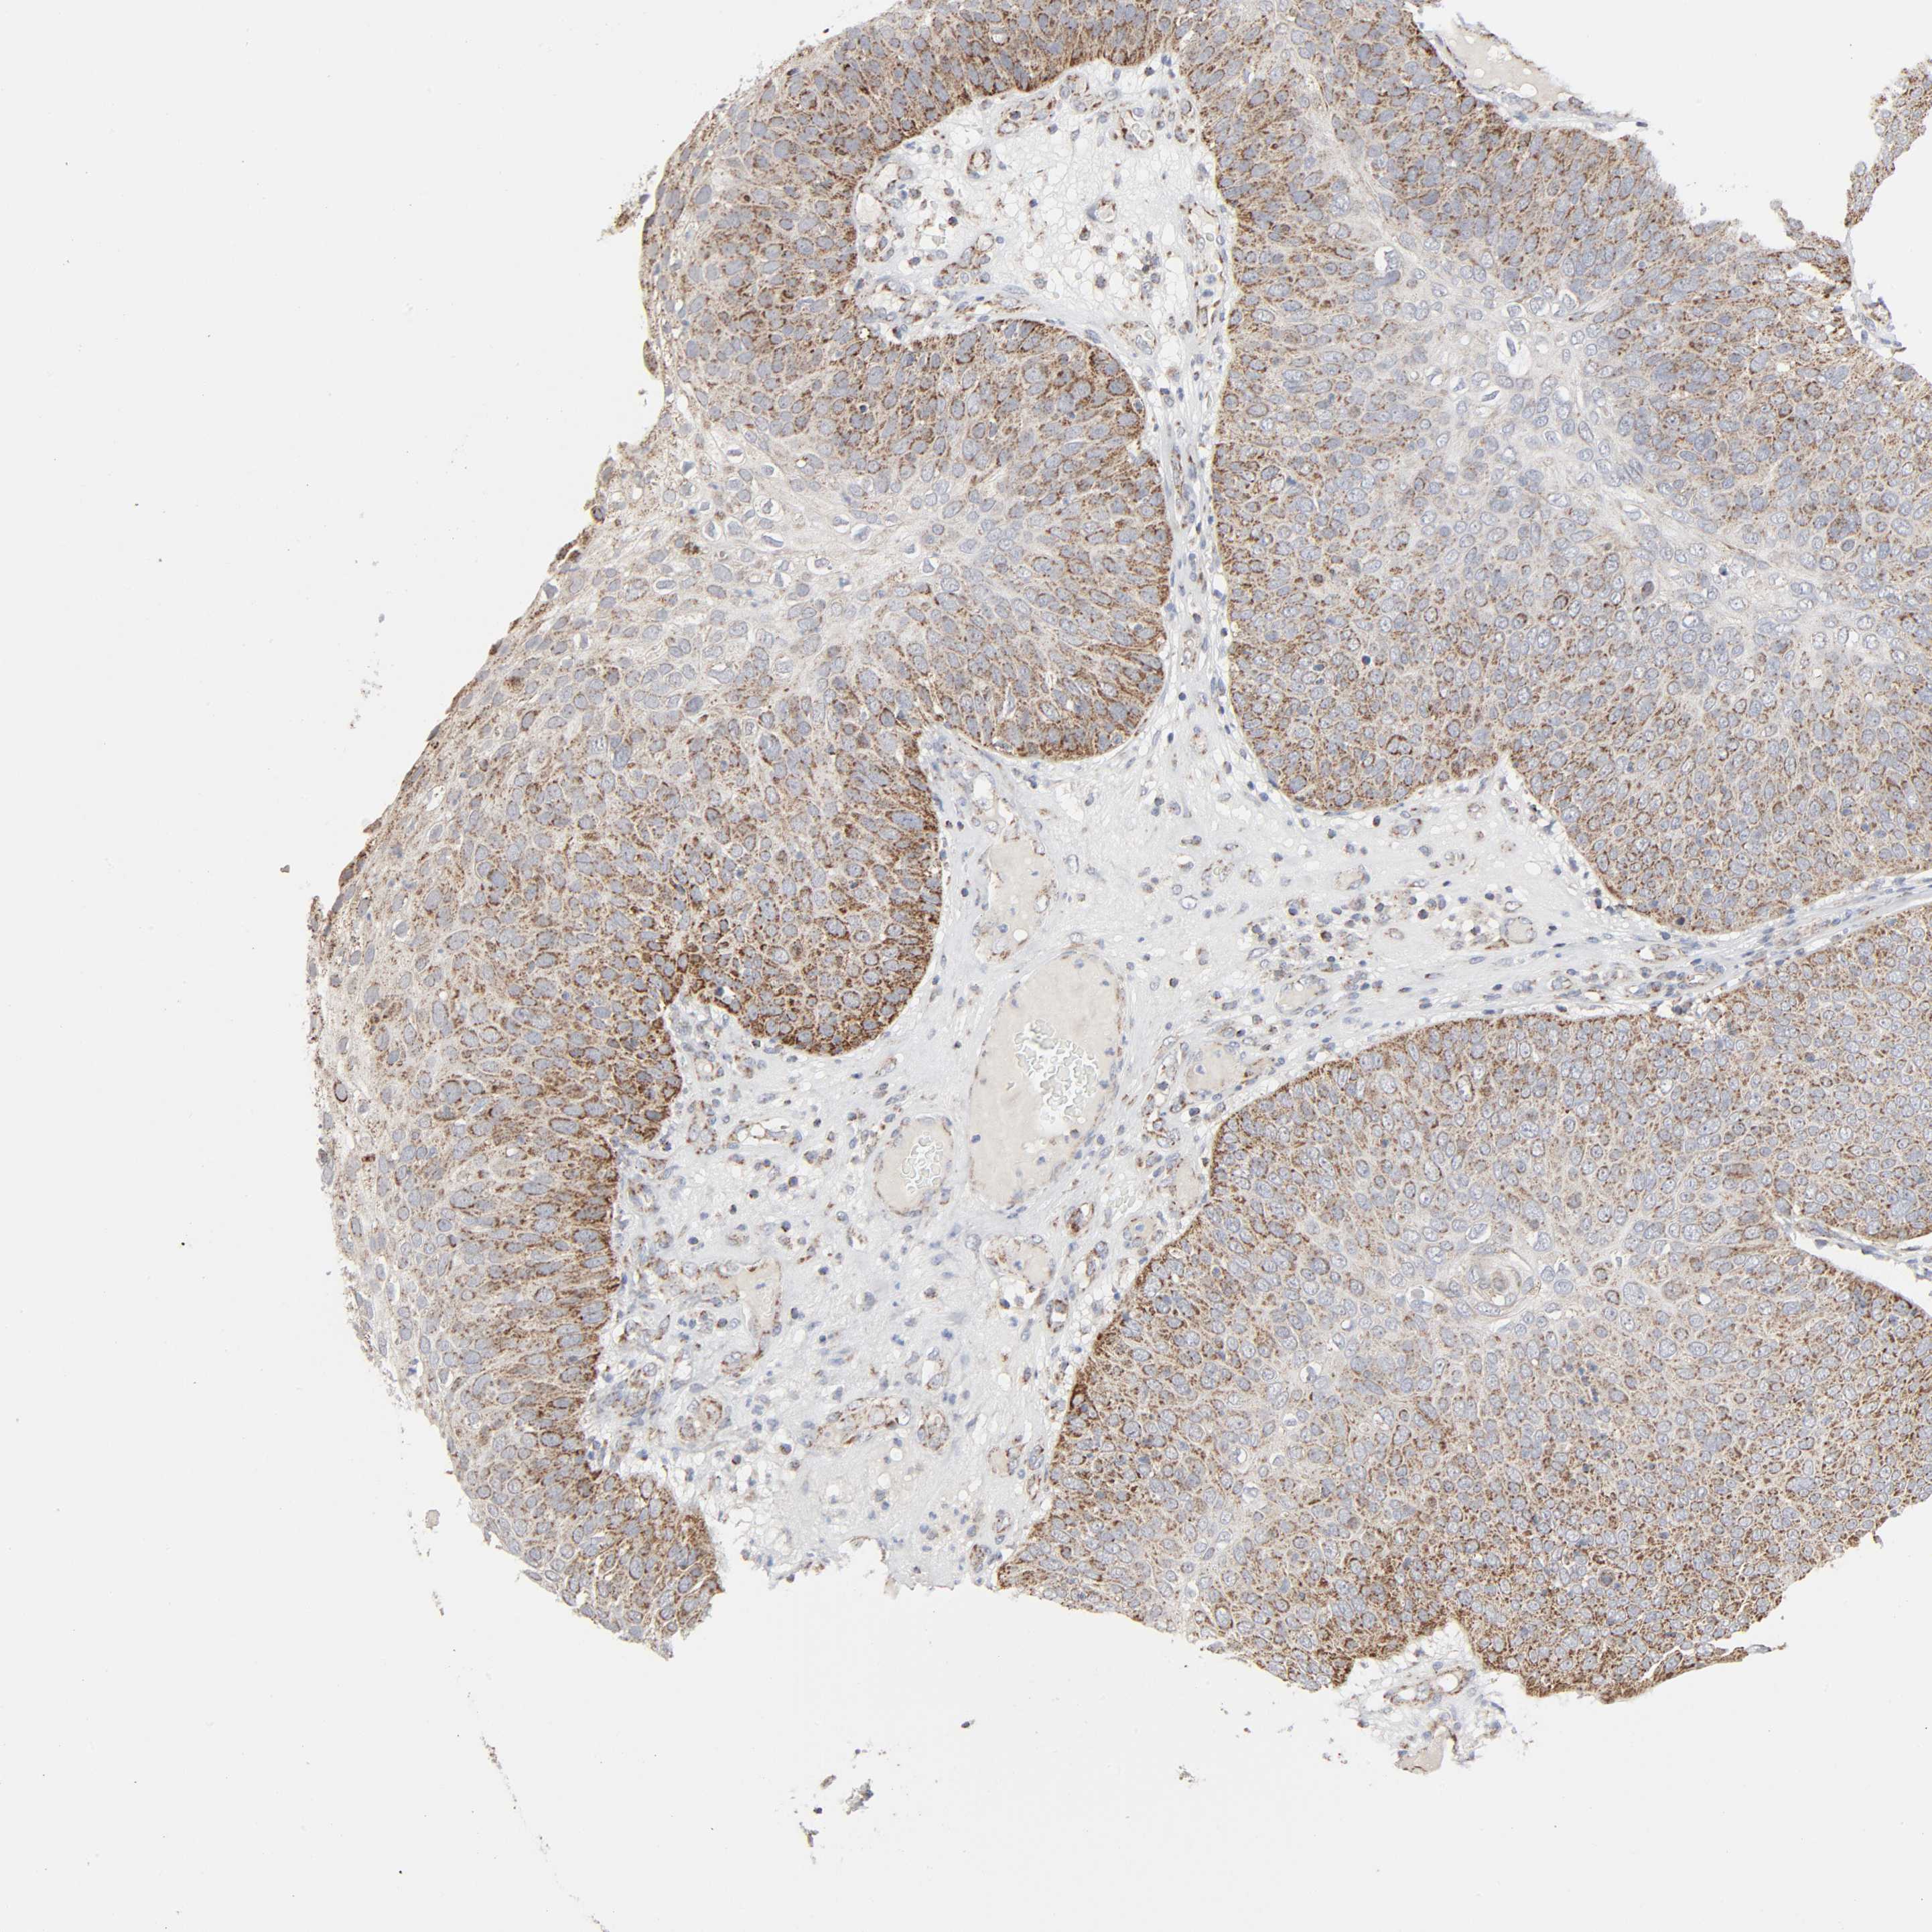

SKIN CANCER - Protein expressioni

A mouse-over function shows sample information and annotation data. Click on an image to view it in a full screen mode. Samples can be filtered based on level of antibody staining by selecting one or several of the following categories: high, medium, low and not detected. The assay and annotation is described here.

Antibody staining in the annotated cell types in the current human tissue is reported as not detected, low, medium, or high, based on conventional immunohistochemistry profiling in selected tissues. This score is based on the combination of the staining intensity and fraction of stained cells.

Each image is clickable and will lead to virtual microscopy that enables deeper exploration of all samples and also displays staining intensity scores, fraction scores and subcellular localization as well as patient and tissue information for each sample.

Antibody HPA076871

Basal cell carcinoma